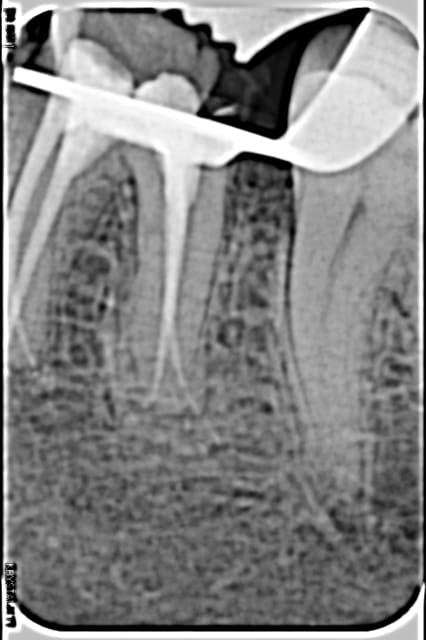

Moins impressionnant que les cas d'esthétique des pages précédentes mais je suis content de mon endo 4 canaux ;)

O 02e7d4f0bd462f70 0 cmqift - Eugenol

O 1958718cc4fe96b5 0 bjixou - Eugenol

As-tu une radio de cette dent reconstruite ?

J'espère que tu as prévu une élongation coronaire en distal.

ça va, il y a de l'os.

Edit: c'est peut-être aussi un artéfact avec le métal du clamp, bien que sur la 1ere radio on semble bien être en sous-crestal.